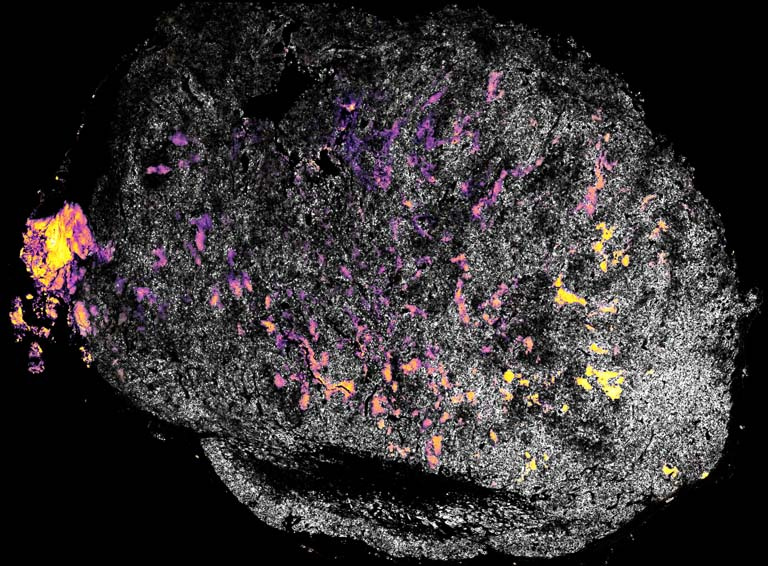

Our work focuses on improving the persistence of protein-based cancer therapeutics in tumors using the FDA-approved vaccine adjuvant (alum). The images all depict the distribution and retention of drug-loaded alum particles delivered intratumorally to the tumor after treatment for two distinct immunostimulatory cytokines therapy – Interleukin-2 (IL-2) and Interleukin-12 (IL-12). Current immunocytokine therapeutic approaches have poor retention properties, which leads to instant leakage from the tumor into systemic circulation. This leads to adverse effects and toxicity issues for patients. Our strategy of loading the cytokines to alum helps promote sustained delivery and better spatial distribution of the cytokines to promote T cell activation within the tumor and preventing leakage and systemic toxicity. These images were taken to illustrate the in vivo pharmacokinetics and intratumoral distribution of alum-tethered cytokine therapy (with IL-2 and IL-12).